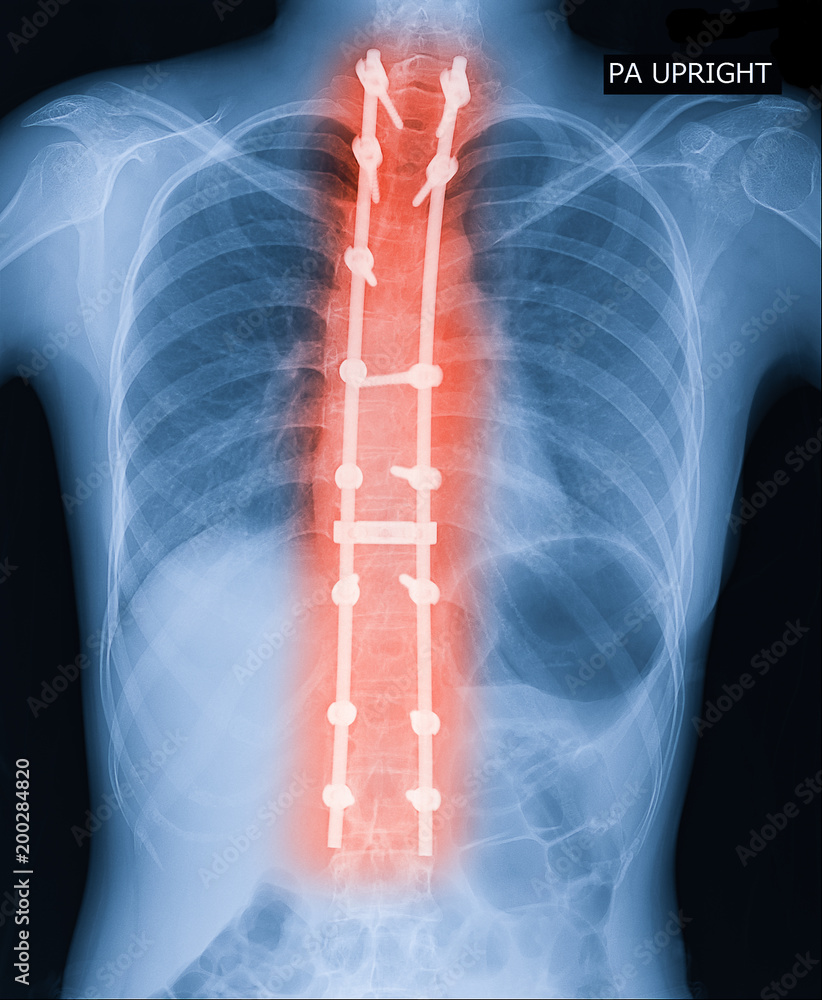

From stock.adobe.com

Xray image of adult patient spine show Scoliosis surgery fix by long Steel Rod Back Surgery During spinal fusion, a surgeon places bone or a bonelike material in the space between two spinal bones. Rod based systems consist of several components which work together to provide immobilization and stabilisation of spinal segments. The vertebrae support each other, with the goal of reducing pain and easing. Preventing movement helps to prevent pain. Spinal fusion is a surgery. Steel Rod Back Surgery.